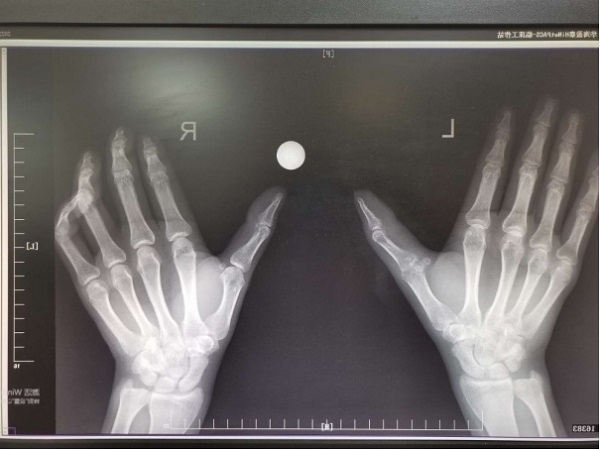

在生活中,有很多中老年人长期受类风湿性关节炎困扰,掌指关节,指间关节,趾趾关节,趾间关节这样的“小”关节是主要侵袭对象。受累以后,手指或足趾关节增粗变形,反复疼痛、活动受限,很多病人深受折磨。 近期,二...